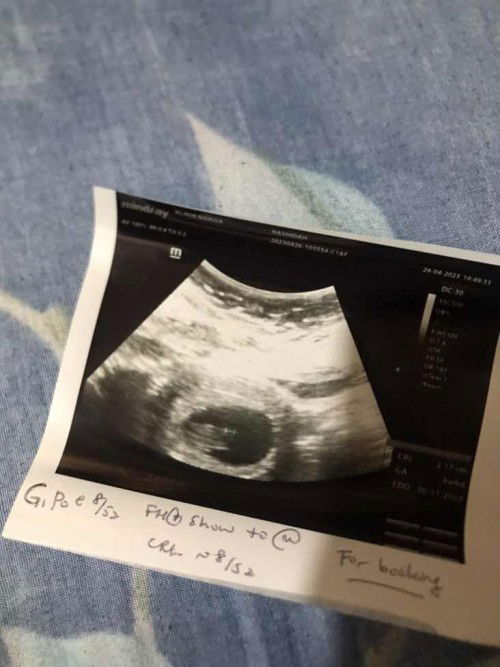

8 week 6 days

Hi saya baru scan untuk buka pink, janin saya 8 week 3 days tapi scan tu detect 8 week 6 days tapi saya nk tahu baby terbentuk nampak kepala tangan berapa week ya? Awak semua tgk scan saya okey tak 😂 tadi dr bagi dengar heartbeat baby, dia kata dah boleh buat buku pink. Sebelum nk check takut sebab ni 2nd baby, dulu 6 week gugur sendiri 😪 #ingintahu #firstmom #bantusharing